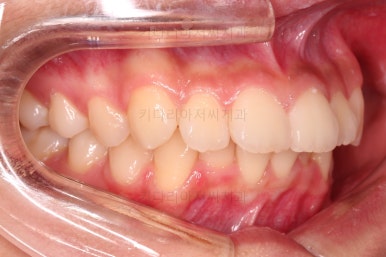

부산치아교정치과 키다리아저씨치과에서 마무리한 입안의 모습입니다.

가지런하게 잘 정렬이 되었고요.

윗니만 발치한 편악발치교정이지만 틈새 없이 공간이 닫혔으며 교합도 잘 맞습니다.

위아랫니가 가지런하게 보기 좋게 배열이 되었고요.

아랫니까지 윗니를 넣음으로써 튀어나와 보이던 앞니의 느낌이 좋아졌습니다.

물론 작은 아래턱에 맞춰 윗니를 뒤로 집어넣어야 해서 자칫 지나치게 들어간 입이 될까 염려되는 조심스러운 케이스였지만, 편악발치를 통해 최소한으로 입을 넣으면서 굉장히 조화롭게 잘 마무리 했습니다.

옆 라인도 움푹 들어가 있던 아랫입술 아랫 부분이 완만하게 펼쳐지면서 입매도 많이 좋아졌습니다.